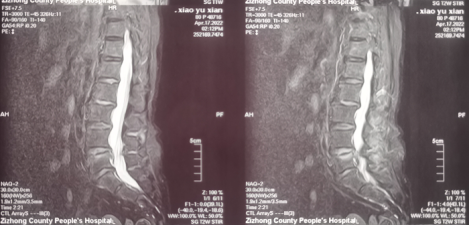

经多轮打听,晓婆婆慕名来到我院骨科,经过详细问诊、查体及相关辅助检查,被确诊为“L4-5椎间盘左侧突出伴椎管狭窄伴不全神经损害”。

鉴于患者高龄,无法承受传统开放手术打击,微创椎间孔镜手术是该病的最佳治疗手段,骨科经过术前评估和准备,于2022年04月20日在麻醉下晓婆婆实施了椎间孔镜微创手术,手术持续约1个小时,手术切口仅7mm,术中出血约5ml,皮内美容缝合一针,无需拆线。术后患者腰痛及左下肢疼痛麻木消失;术后第二天即可下地行走。

(图片可点击放大查看)